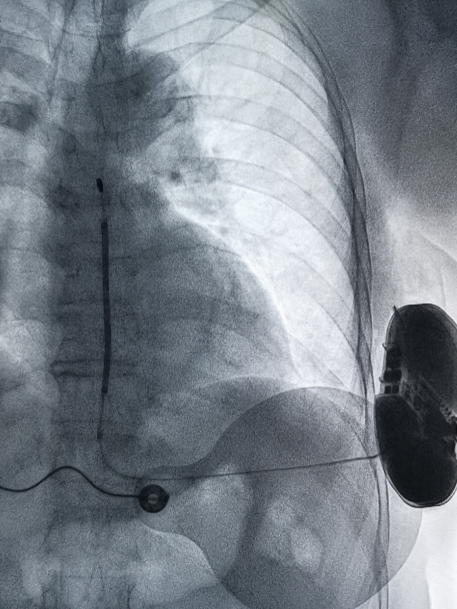

术后影像